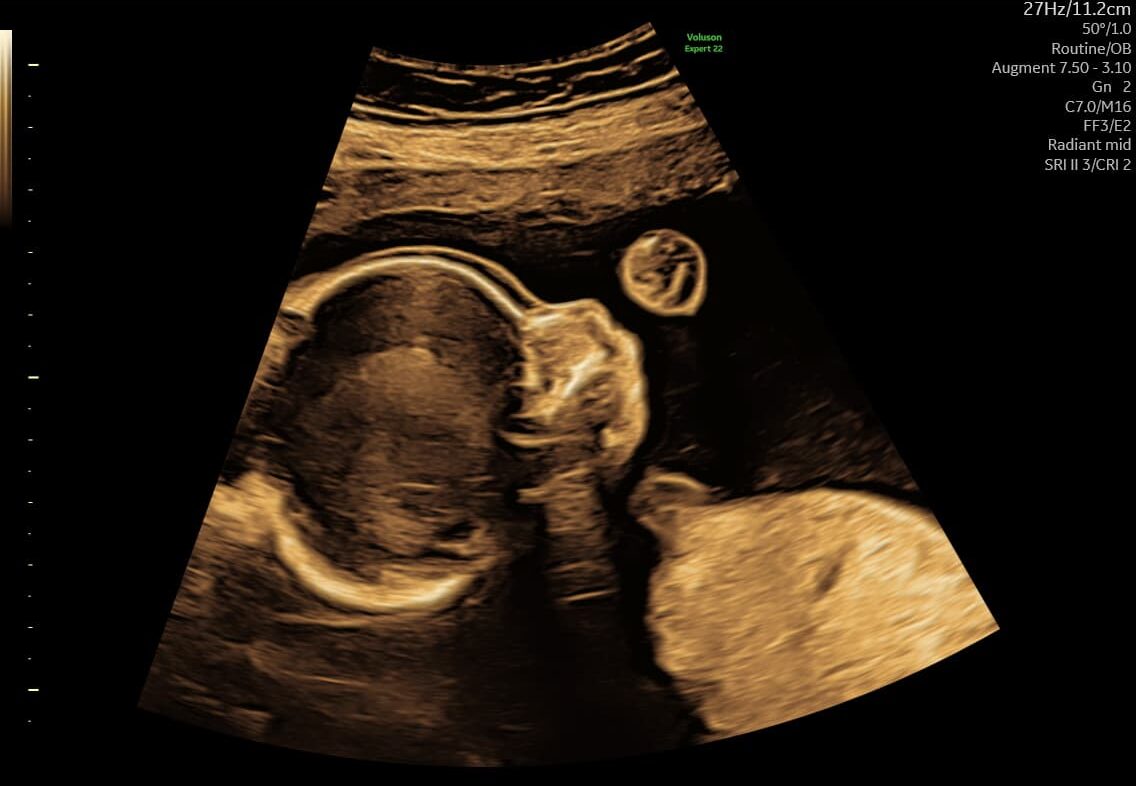

Ved en tryghedsscanning fra uge 14+0 vurderer vi blandt andet:

- hjerteaktivitet

- bevægelser

- fostervand

- moderkagens placering

- generel trivsel

Vi vurderer bl.a. hjerteaktivitet, bevægelse, fostervandsmængde, moderkagens placering og generelle trivselstegn.